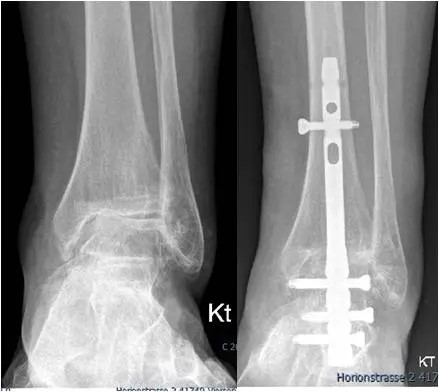

Gelenkersetzende Verfahren: Diese genannten Maßnahmen sind bei sehr fortgeschrittenen Degenerationen mit deutlicher Einschränkung der Beweglichkeit nicht mehr möglich. Dann bietet sich ein gelenkopferndes Verfahren an. Dabei wird unterschieden zwischen einer Versteifung (Arthrodese) des Sprunggelenks oder einer Sprunggelenksprothese. Die Arthrodese des Sprunggelenkes bietet den Vorteil, dass es sich dabei um eine endgültige Behandlung handelt, d.h. dass bei erfolgreich versteiftem Gelenk keine weiteren Operationen im Bereich des oberen Sprunggelenkes erforderlich sind. Der Nachteil besteht vor allem in einer Beeinträchtigung des Gangzyklus durch die Stilllegung des Gelenkes.

Schwere OSG Arthrose mit Verkippung des Talus, operativ versorgt mittels einer Nagelarthrodese